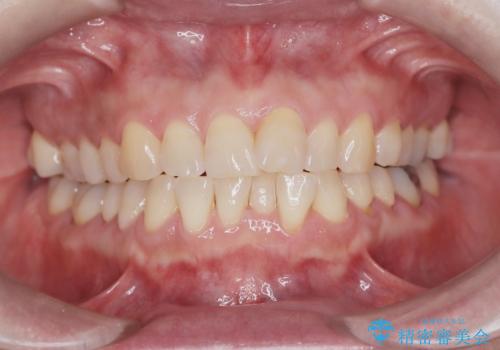

前歯の突出と下顎の偏位を改善。審美ワイヤーで整えるバランスの良い歯並び